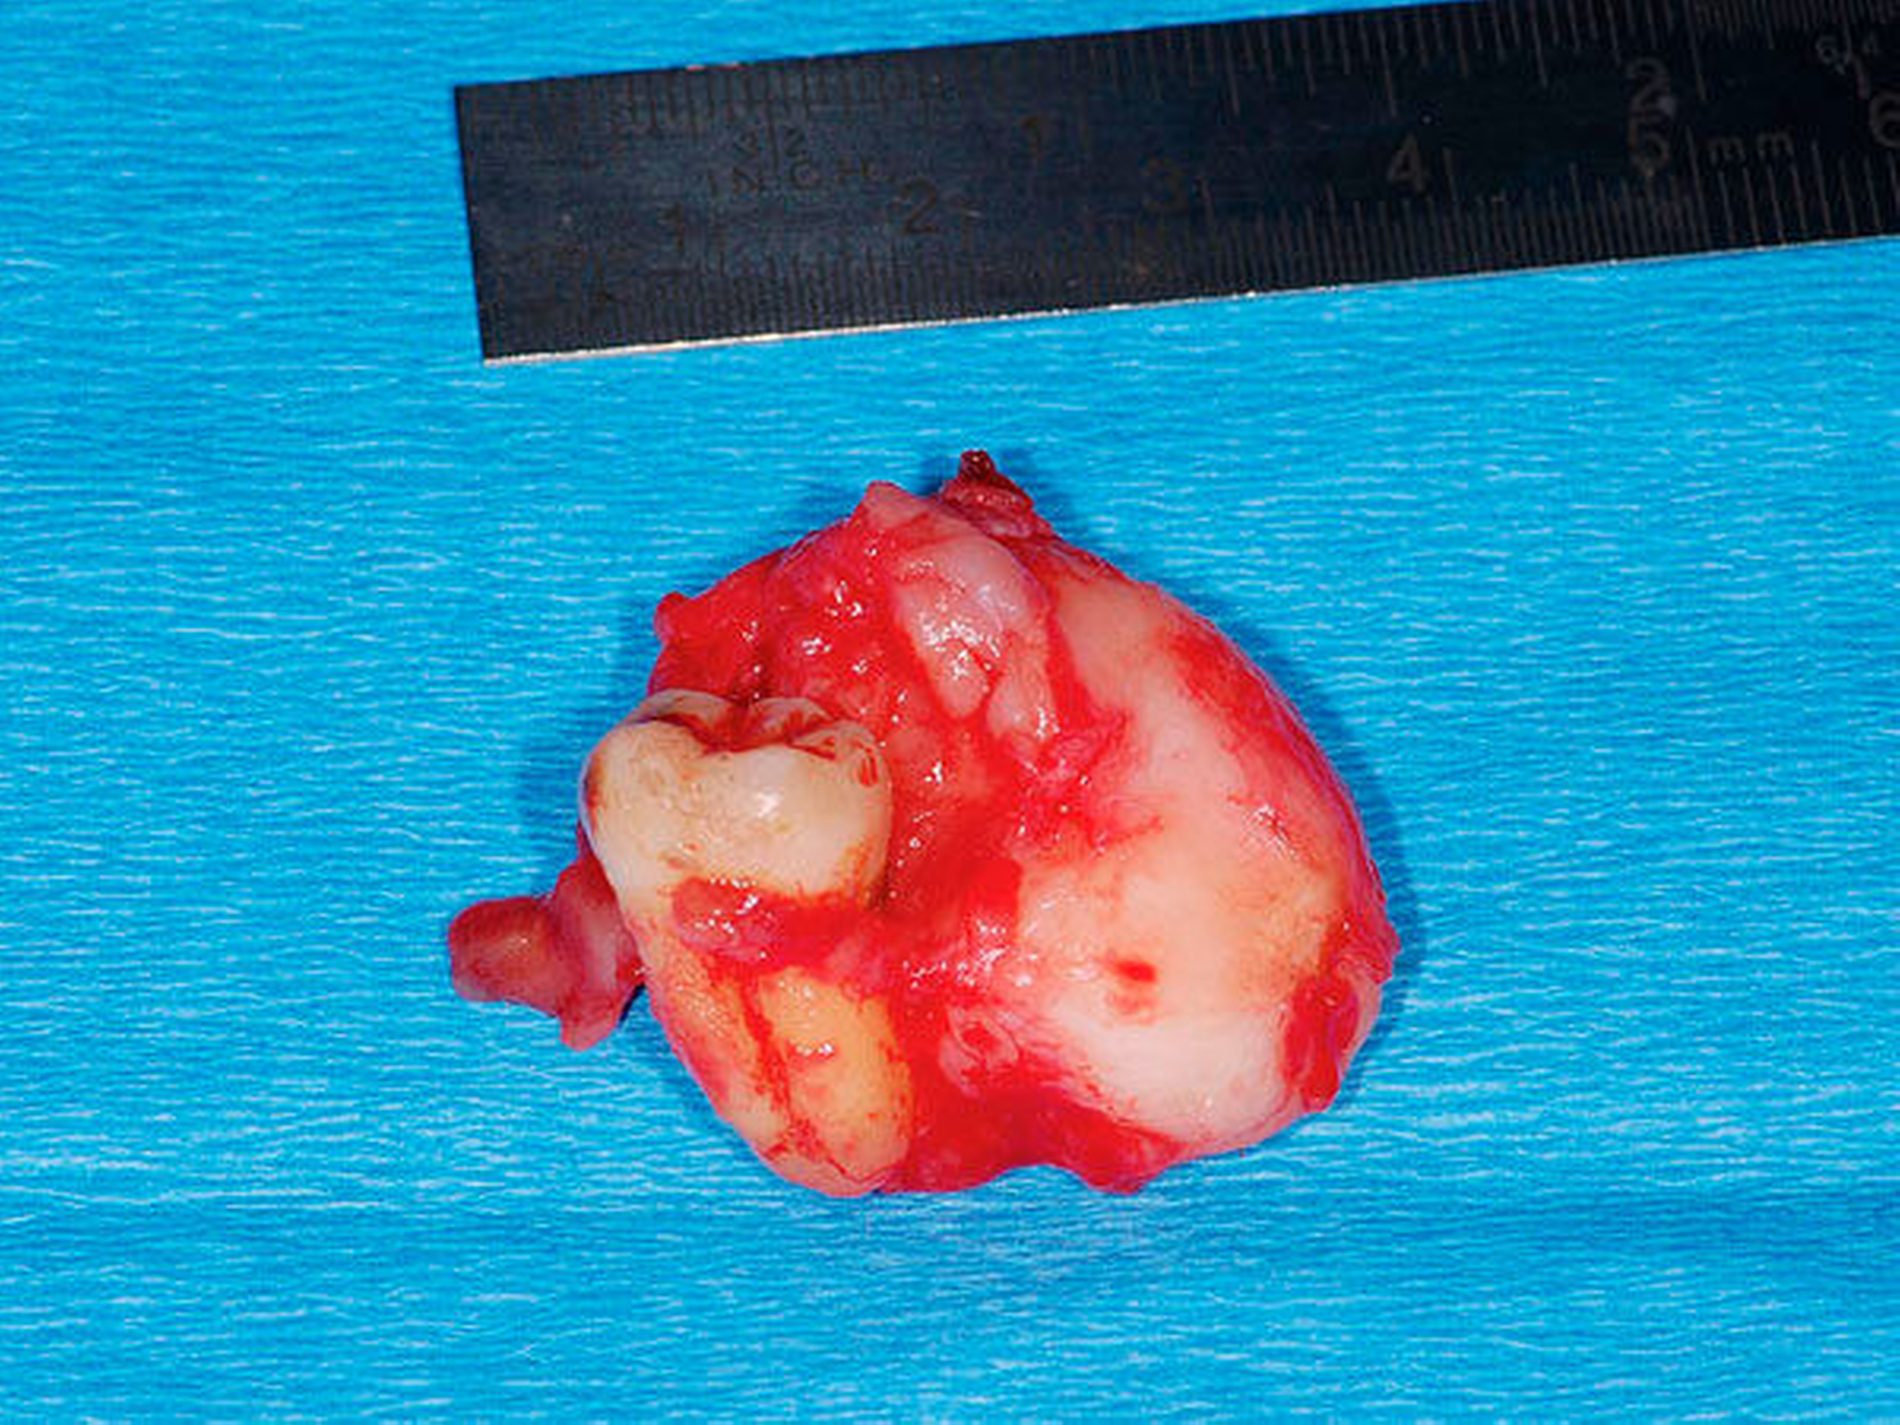

Nach Aufklärung des Patienten umfasste die Therapie der Wahl die In-toto-Resektion des Befunds zusammen mit der Extraktion der Zähne 47 und 48. In Intubationsnarkose erfolgte eine mesiale Schnittführung an 47/48 mit Entlastungen im Bereich des aufsteigenden Astes und nach vestibulär. Zu sehen war eine derbe, weißliche und adhärent mit 48 verwachsene Läsion (Abbildung 3), die gemeinsam mit dem Zahn entfernt wurde (Abbildungen 4 und 5). Der Zahn 47 wurde ebenfalls extrahiert und nach Kürettage und Glättung der Knochenkanten ein Kollagenflies in den Defekt eingelegt. Die anschließende plastische Deckung erfolgte mehrschichtig (Abbildung 6).

Die histologische Aufarbeitung des etwa 3 cm x 2,5 cm x 2 cm großen Resektats ergab ein spindelzelliges Proliferat mit myxoidem Stroma (Abbildung 7) und Arrosionen des ortsständigen Knochens. Zur weiteren histogenetischen Typisierung wurde ergänzend eine immunhistochemische Untersuchung durchgeführt, die die Diagnose des odontogenen Myxofibroms bestätigte. Bei einem Nachsorgeintervall von insgesamt sechs Jahren zeigte sich sowohl klinisch als auch radiologisch kein Anhalt auf ein Rezidiv.